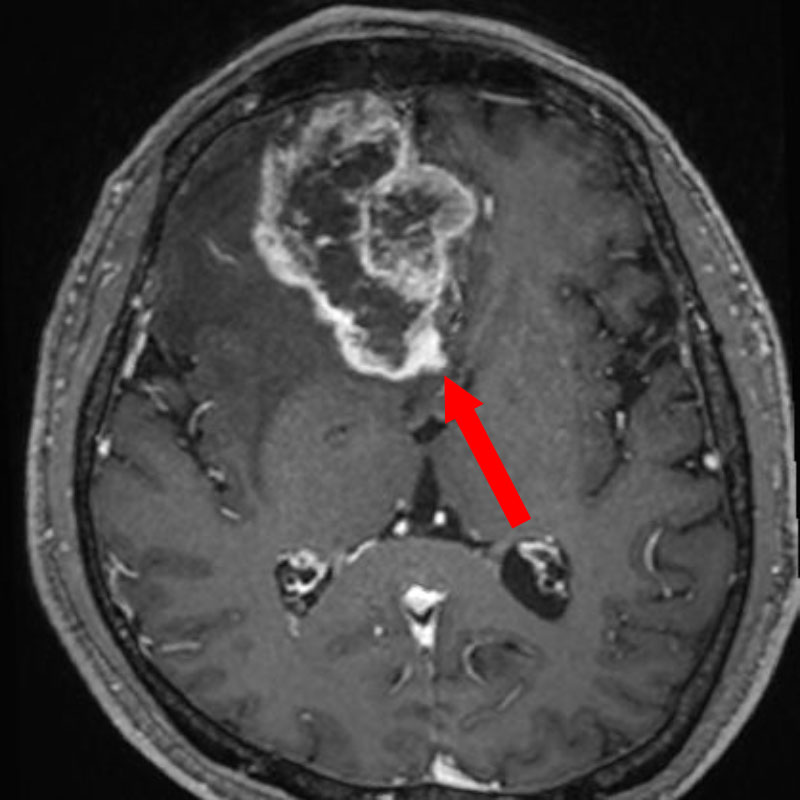

624

'25年4月

70代

後頭葉膠芽腫

頭蓋内腫瘍摘出術

No.’25_26 手術前1

No.’25_26 手術前2

No.’25_26 摘出 前

No.’25_26  摘出 中

No.’25_26 摘出 後